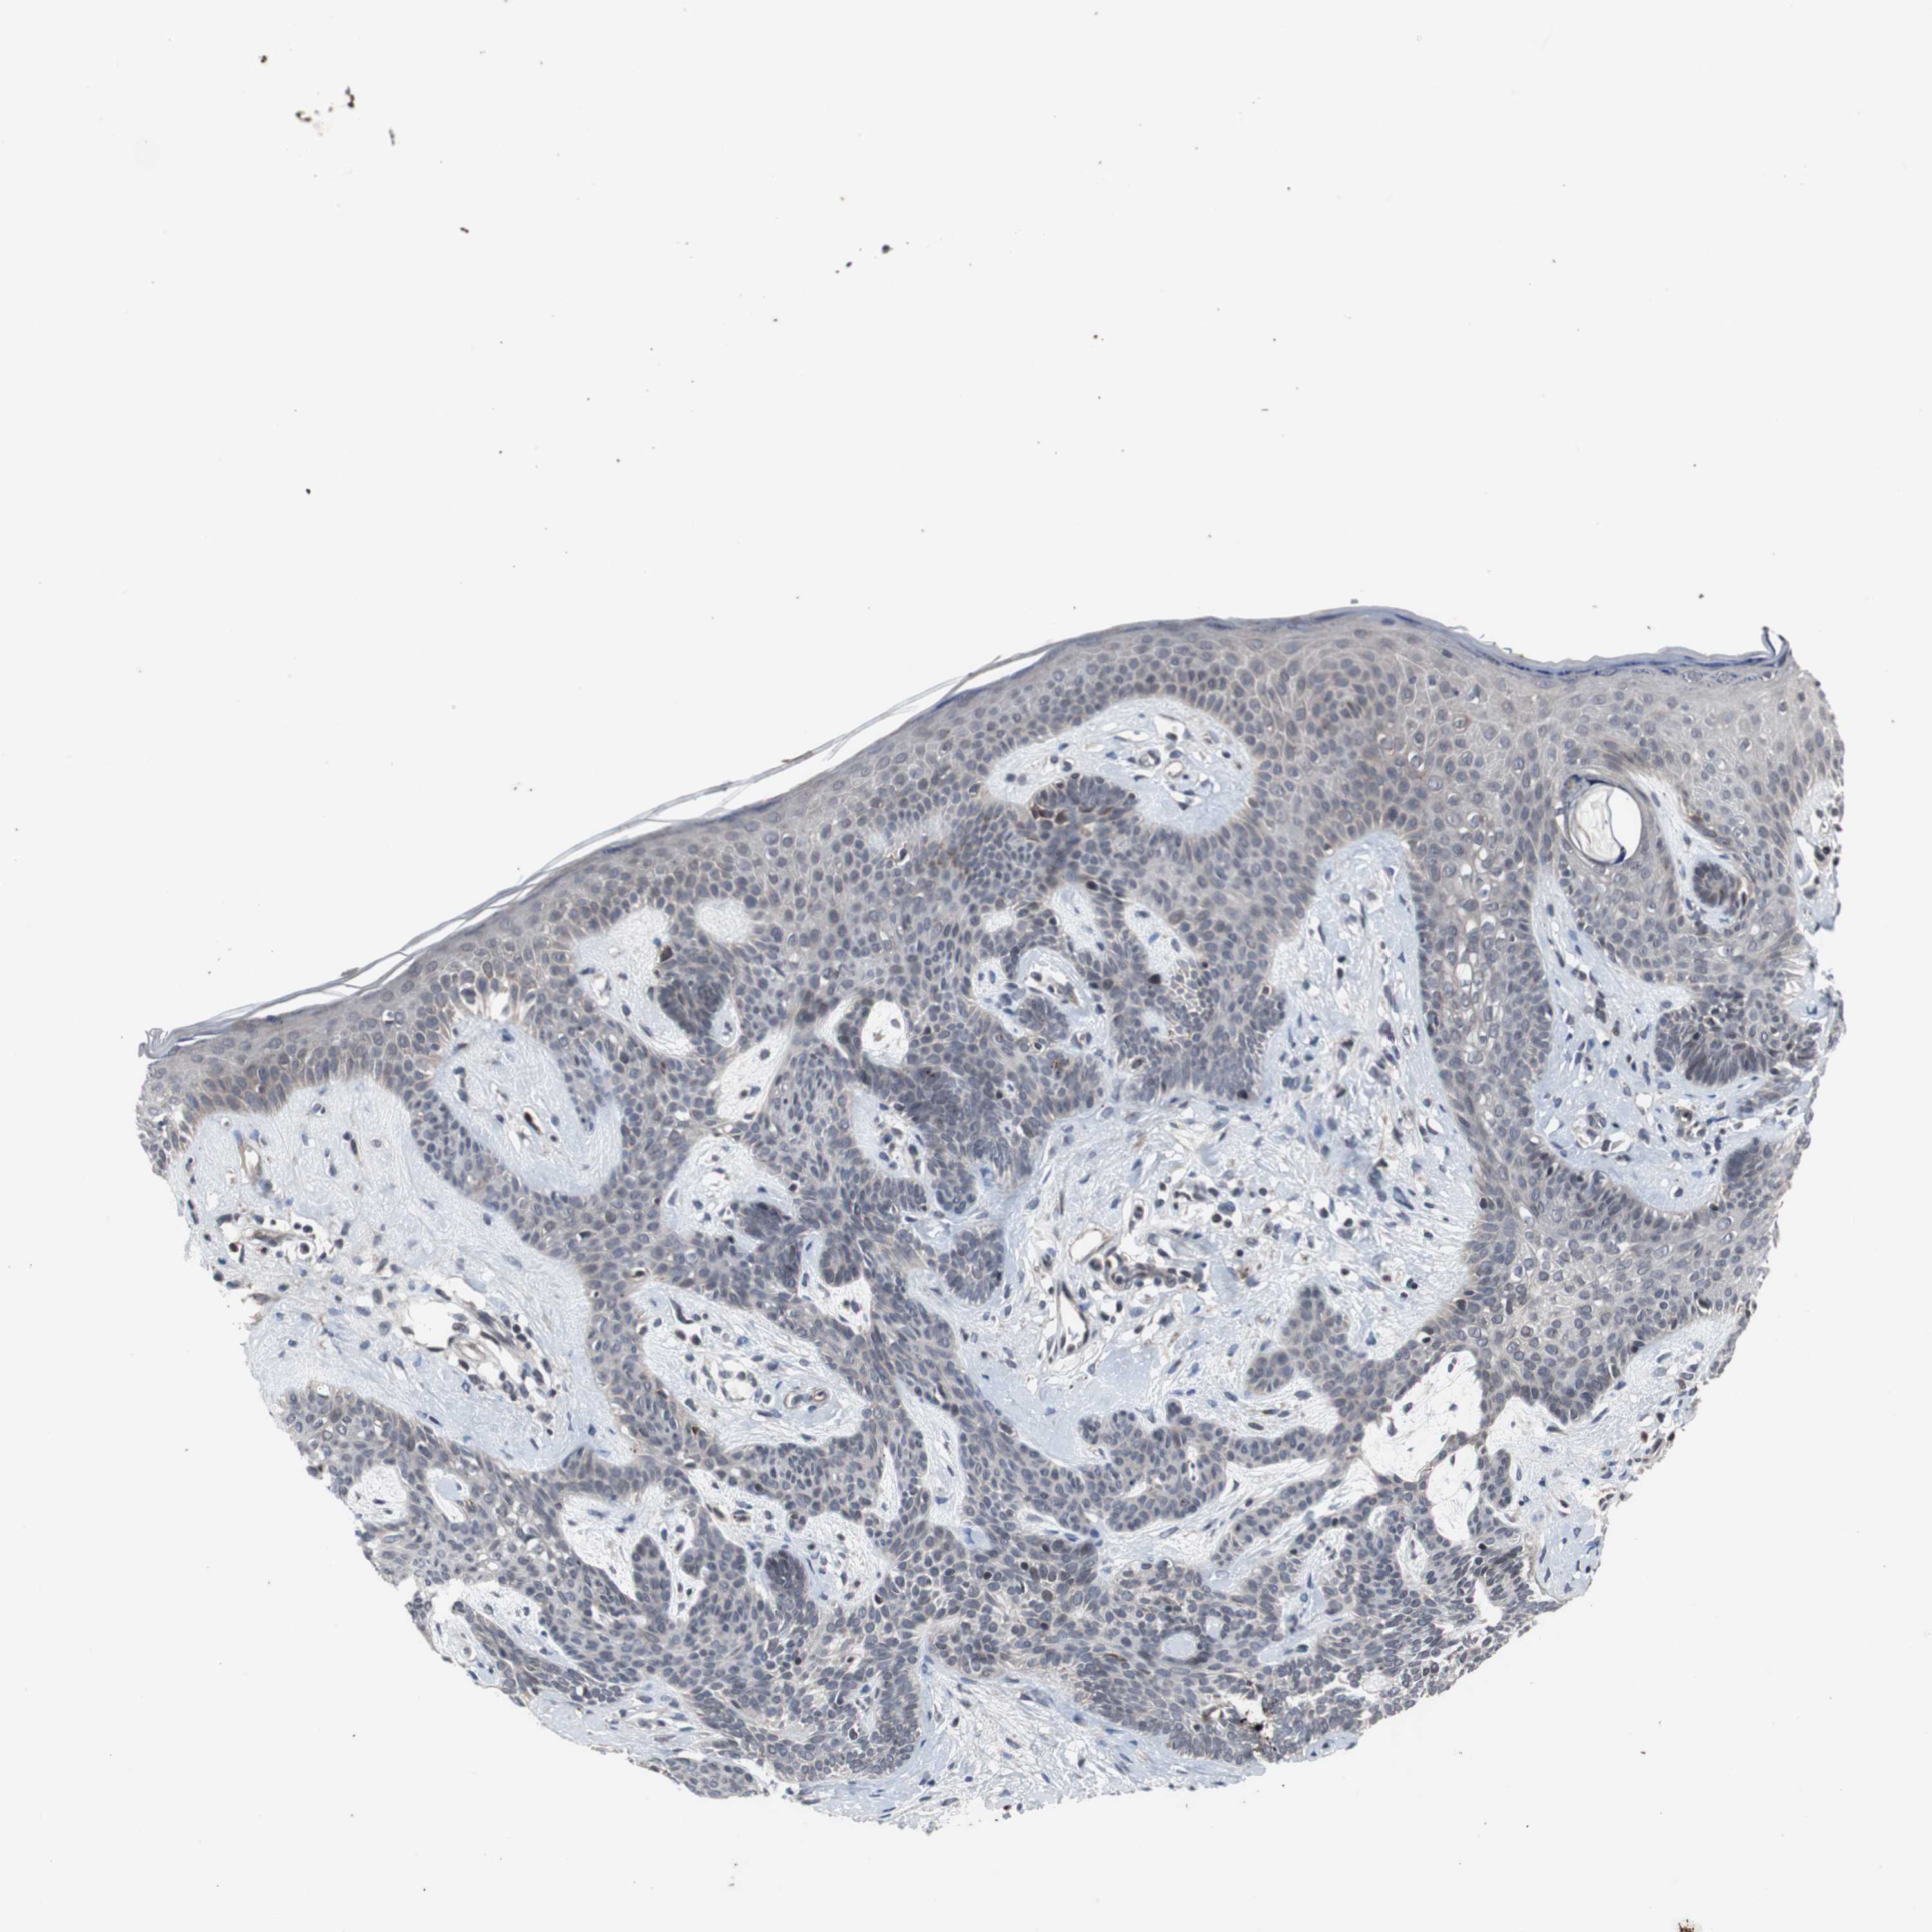

Antibody CAB005337

Staining

High

Medium

Low

Not detected

Intensity

Strong

Moderate

Weak

Negative

Quantity

>75%

75%-25%

<25%

None

Location

Nuclear

Cytoplasmic/membranous

Cytoplasmic/membranous,nuclear

Squamous cell carcinoma, NOS

Squamous cell carcinoma, metastatic, NOS

Basal cell carcinoma

Papilloma, NOS